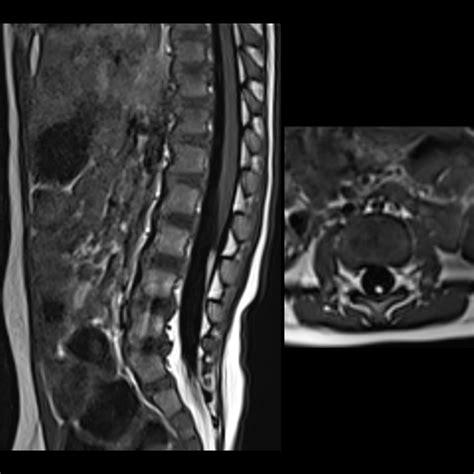

Tethered Cord MRI plays a pivotal role in the diagnosis of tethered cord syndrome. This imaging technique uses magnetic fields and radio waves to produce detailed images of the spinal cord and surrounding structures. Unlike traditional MRI, Tethered Cord MRI focuses specifically on the spinal cord, providing high-resolution images that can detect even the slightest abnormalities.

One of the key advantages of Tethered Cord MRI is its ability to visualize the spinal cord in multiple planes. This allows radiologists to get a comprehensive view of the spinal cord and identify any areas where it may be tethered. The images obtained from Tethered Cord MRI are also highly detailed, making it easier to pinpoint the exact location and extent of the tethering.

After the Tethered Cord MRI procedure, the images will be reviewed by a radiologist who specializes in interpreting MRI scans. The radiologist will look for signs of tethered cord syndrome, such as:

• Abnormal Attachments: The spinal cord may be attached to surrounding tissues, such as the dura mater or vertebrae, in an abnormal manner.

• Thickened Filum Terminale: The filum terminale is a thin, fibrous structure that anchors the spinal cord. In tethered cord syndrome, this structure may be thickened or shortened.

• Spinal Cord Stretching: The spinal cord may appear stretched or elongated, indicating that it is being pulled down by the tethering.

• Other Abnormalities: The radiologist may also look for other abnormalities, such as spinal cord tumors, cysts, or malformations, that could be contributing to the symptoms.